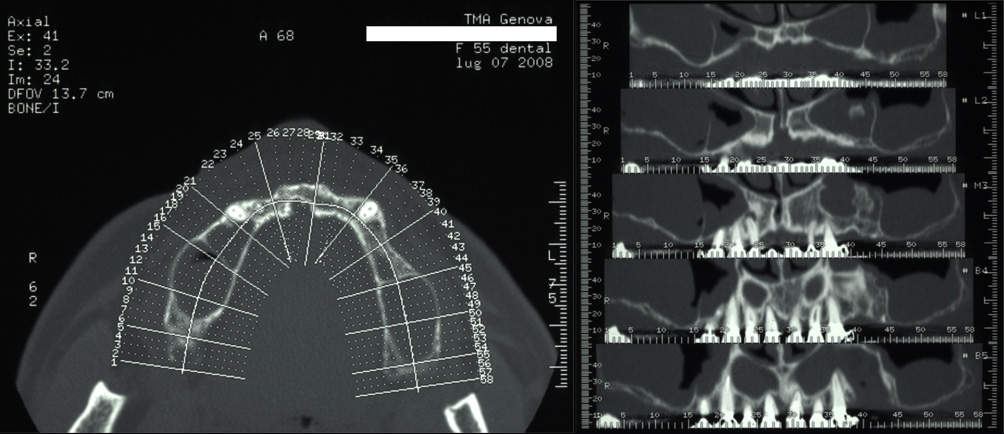

Rigenerazione ossea del pavimento del seno mascellare con incremento verticale di 12 mm ed orizzontale di 10 mm